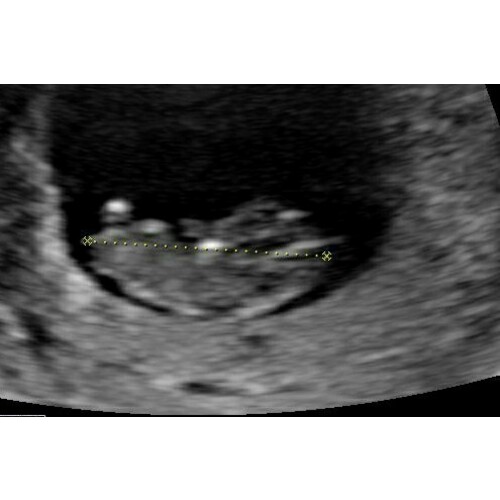

Mooie echo foto! Dat hummeltje groeit lekker zorgeloos in jouw buik. Hopelijk kun jij er snel zorgeloos van gaan genieten ;)